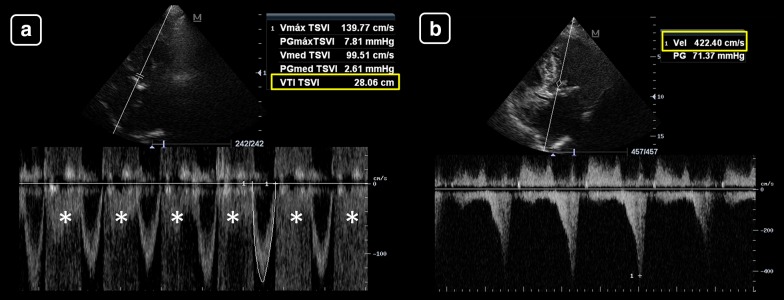

The LVOT VTI is not reliable for estimating the SV/CO when there is a moderate-to-severe aortic regurgitation (AR) and/or a subaortic obstruction (LVOTO, fixed and/or dynamic) [19] (Fig. 7). Dynamic LVOTO may be observed in extreme hypovolemia, asymmetric left ventricular septal hypertrophy (specially at a low preload and high inotropic stimulation), anterior myocardial infarctions with compensatory hyperdynamic basal segments of the interventricular septum [19] and in Takotsubo syndrome [34]. Dynamic LVOTO and AR produce high LVOT velocities/VTI and thus overestimated VTIs. Also, for assessing the response to treatments, there is no certainty regarding whether the changes in the LVOT VTI result from an increased SV or from an increased regurgitant volume (AR) or subaortic obstruction (LVOTO).

Fig. 7.

a Left ventricular outflow tract velocity–time integral (LVOT VTI) in severe aortic regurgitation. LVOT VTI showed high values (yellow box), overestimating the stroke volume. Asterisks: aliased spectral Doppler signal of aortic regurgitation. b LVOT VTI in dynamic LVOT obstruction, obtained with continuous wave Doppler (pulsed-wave Doppler waveforms were aliased). The spectral Doppler showed high blood flow peak velocities (4.2 m/s, yellow box) and a long time-to-peak signal. This situation can be seen in severe hypovolemia, hypertrophic cardiomyopathy, anterior myocardial infarctions with hypercontractile basal segments and in Takotsubo syndrome